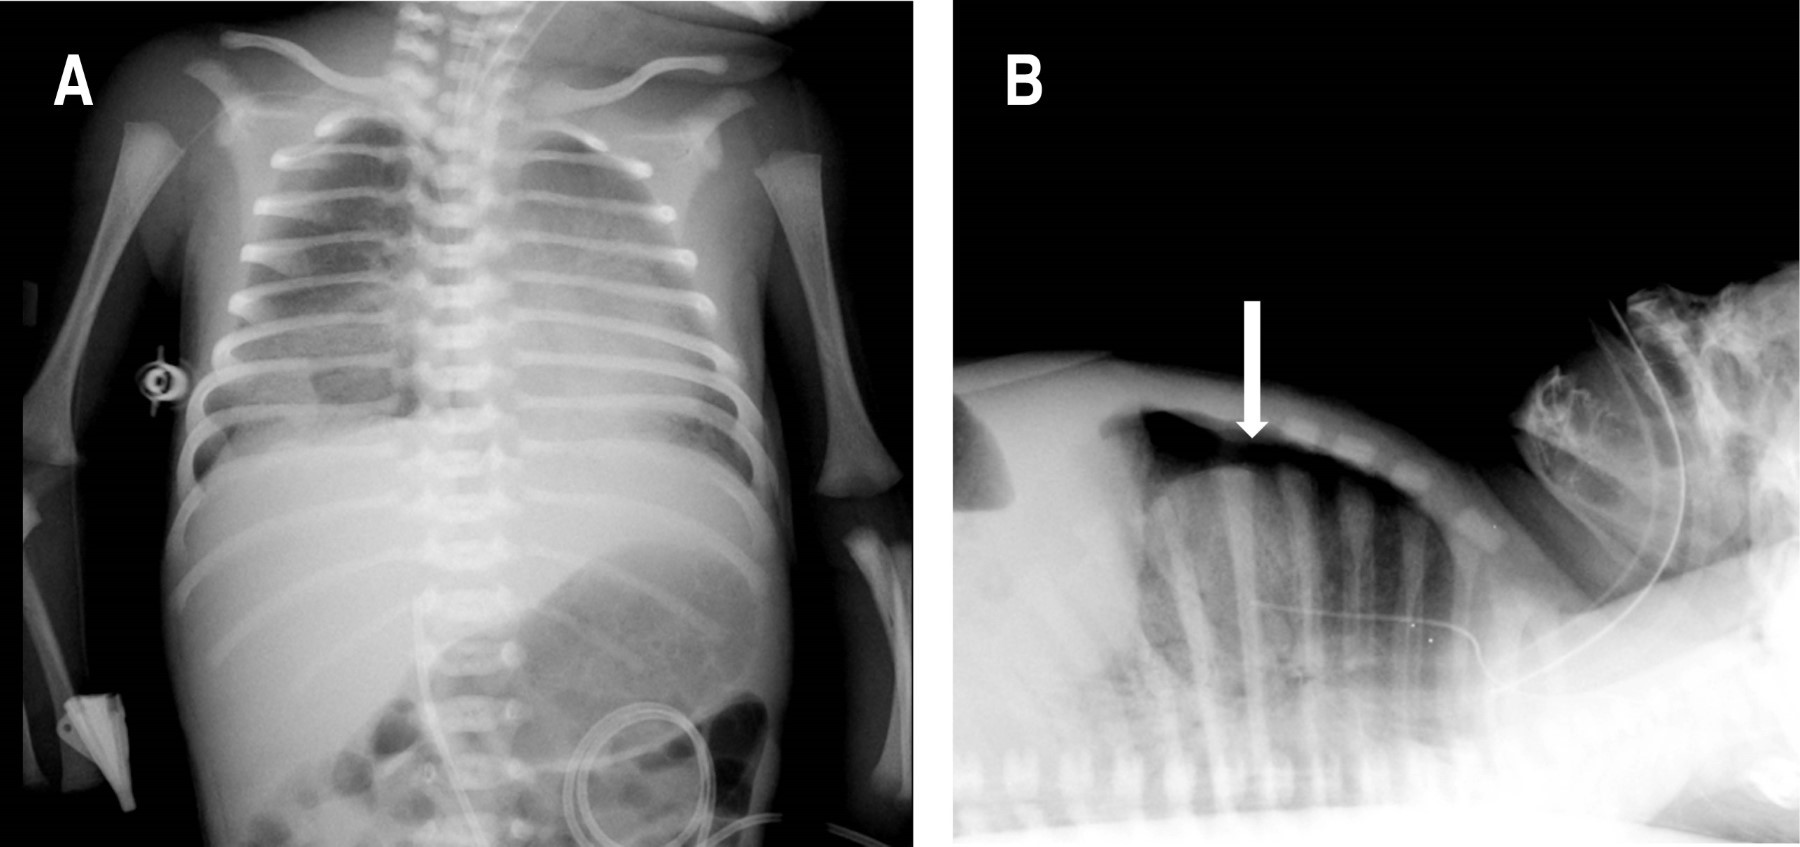

Se procede a realizar UP, como parte del protocolo SAFE,1 observando en la región medial y basal derecha la presencia de neumotórax (Figura 1); mientras que en la región lateral derecha y en el hemitórax izquierdo no se identificaron anormalidades. Cabe señalar que el neumotórax no era visible en la radiografía anteroposterior de tórax, por lo que se solicita radiografía lateral en la cual sí se evidencia el neumotórax anterior (Figura 2).

Figura 1